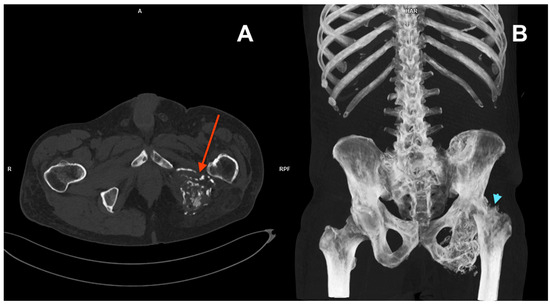

Upon presentation in August 2023, a CT scan revealed a subcapital fracture of the left femoral neck in the healing phase (Figure 3). The retrospective reassessment of the previous CT performed in April 2023 demonstrated an early stage of femoral neck fracture at the border of the examination range. There was no history of trauma and only mild exacerbation of pain during weight bearing. After consultation with an orthopaedic surgeon, the treatment was abandoned due to the presence of cancer-related changes in the pelvis, the stable nature of the fracture, and the patient’s compromised mobility, which allowed him to function despite the unnoticed fracture. Furthermore, surgery would likely involve significant challenges, including a questionable prognosis for successful healing. The second course of palliative RTH on the pelvis area (30 Gy in 10 fractions) was administered in April 2024. Currently (Figure 4), the patient is continuing therapy with sirolimus and pamidronate, remaining professionally active (November 2024).

Figure 3. CT scans from September 2022 (A), January 2023 (B), and April 2023 showing decreased bone density in the left femur and pathological lesions in the vertebrae and left pelvic bones. Early signs of a subcapital fracture of the left femoral neck (red arrow) first seen in the CT from April 2023 (C).

Figure 4. CT scan from August 2023 (A) showing extensive lytic infiltration of the left ischium at the initial tumour site (red arrow). Coronal plane maximum intensity projection (MIP) of the same CT (B). Impacted fracture of the left femoral neck (blue arrowhead) caused by the neoplastic infiltration. Pathological lesions in the left ischium and hip bone as well as in ribs 10 and 11 on the right side.